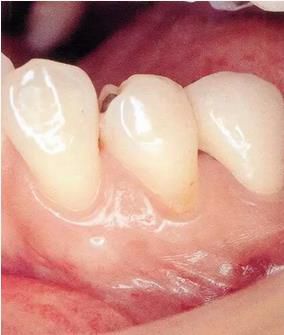

▲圖3

牙位異常例③。邊緣嵴高度不整齊。